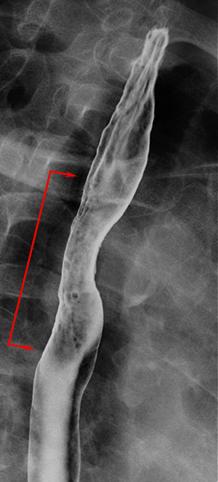

疾病(病理主体)的分类恶性上皮肿瘤/扁平上皮癌

部位(按器官分)食道/中

检查方法X线

肿瘤的肉眼分类0型(表在型)/IIc型(IIc)

肿瘤最大直径40以上

肿瘤的深度m